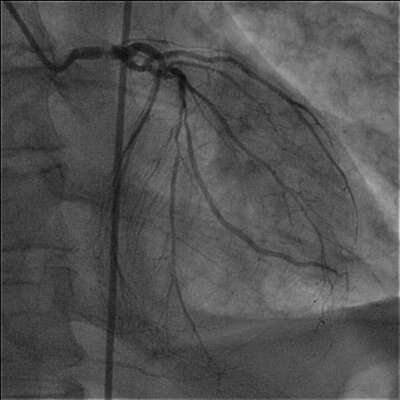

On the basis of elevated troponin I diagnosis of non-ST segment elevation myocardial infarction was made. The patient underwent cardiac catheterization and coronary angiogram which showed 90-95% left main coronary artery stenosis, 90% LAD, 95 % LCx, 90% marginal branch and 98 % dominant RCA stenosis with collaterals from the left system ( two representative views of left coronary artery are presented). There was severe left ventricular systolic dysfunction.

Stenosis left main image 1